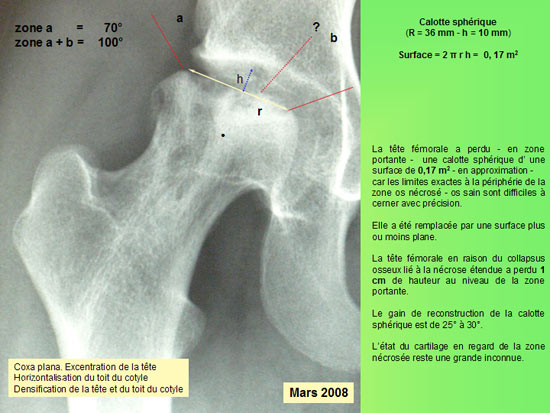

MESURE DE LA SURFACE

Sur le plan radiographique : - La zone nécrotique est nettoyée. - L'aplatissement de la tête fémorale ne s'est pas aggravé depuis l'intervention. - le corail naturel est résorbé au niveau du col ; il est partiellement résorbé au niveau de la tête fémorale.